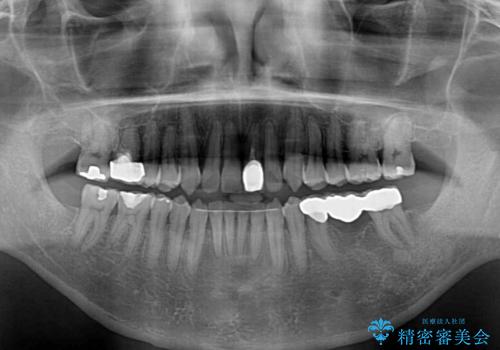

外科処置は希望されなかったので、開咬の改善は限界があると事前にお話ししていたため、上下前歯が完全に接触する前に、もう十分改善したとのことで治療を終了しました。

インビザラインを毎日22時間しっかりと装着してくださったので、我々も驚愕するほどの治療成果が達成されました。